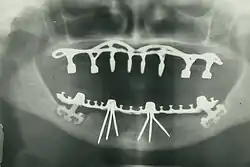

The modern movement of evidence-based dentistry calls for the use of high-quality scientific research and evidence to guide decision-making such as in manual tooth conservation, use of fluoride water treatment and fluoride toothpaste, dealing with oral diseases such as tooth decay and periodontitis, as well as systematic diseases such as osteoporosis, diabetes, celiac disease, cancer, and HIV/AIDS which could also affect the oral cavity. Other practices relevant to evidence-based dentistry include radiology of the mouth to inspect teeth deformity or oral malaises, haematology (study of blood) to avoid bleeding complications during dental surgery, cardiology (due to various severe complications arising from dental surgery with patients with heart disease), etc.

By nature of their general training, dentists, without specialization, can carry out the majority of dental treatments such as restorative (fillings, crowns, bridges), prosthetic (dentures), endodontic (root canal) therapy, periodontal (gum) therapy, and extraction of teeth, as well as performing examinations, radiographs (x-rays), and diagnosis. Dentists can also prescribe medications used in the field such as antibiotics, sedatives, and any other drugs used in patient management. Depending on their licensing boards, general dentists may be required to complete additional training to perform sedation, dental implants, etc.

- Oral and maxillofacial radiology – the study and radiologic interpretation of oral and maxillofacial diseases.